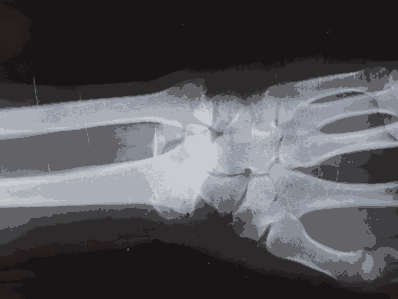

- Common leukaemia symptoms include fatigue, repeated infections, bruising, and bleeding.

- Symptoms like shortness of breath, fever, night sweats, and bone/joint pain can also be indicators of leukaemia.